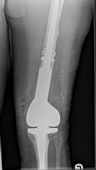

Revision Surgery

In a similar fashion to hips, all knees will eventually wear out. The commonest reason for failure is aseptic loosening, but infection, poor surgery, the wrong implant, can also lead to the knee requiring to be replaced prematurely. Also knee revision implant surgery is increasingly being performed for trauma (fracture) and failed trauma surgery.

Revision of failing implants is a specialist area. Removal of the implant without causing any further damage to the joint and preserving as much bone and soft tissue is critical so that successful reconstruction is possible.